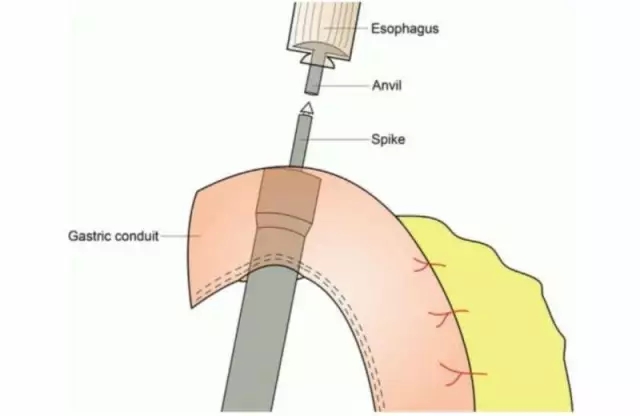

胡迪主任在阐述管型胃手术成功因素时强调,术中保护好胃网膜右动脉和静脉极为重要,很多医生重点关注保护动脉,而保护静脉同样非常重要,因为管型胃只靠胃网膜右动静脉提供血液循环。胃底血供比较差,主要靠胃黏膜下潜行血管提供营养,因管型胃通常比食管缺损长,在食管管型胃吻合后,要切除多余的胃底组织,减少缺血造成的吻合口瘘。

食管管型胃吻合,并切除胃底组织

来自Internet图片搜索